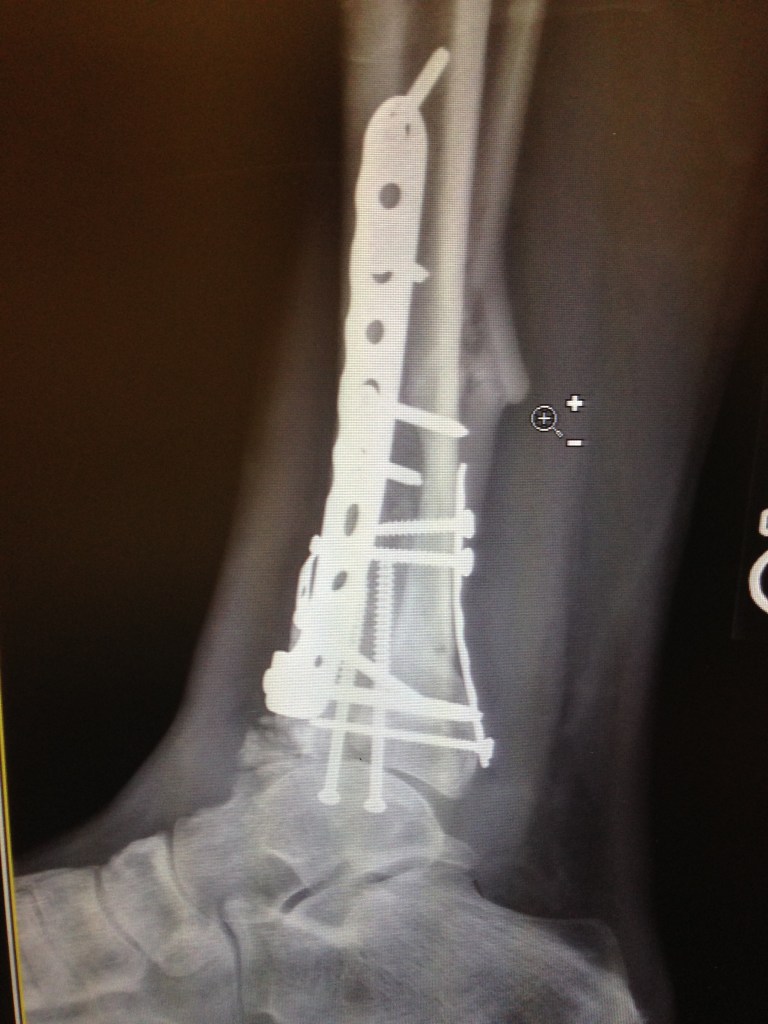

2015-12-04 14.37.25 Published December 6, 2015 at 2448 × 3264 in Ankle replacement not an option, Fusion needs to wait too